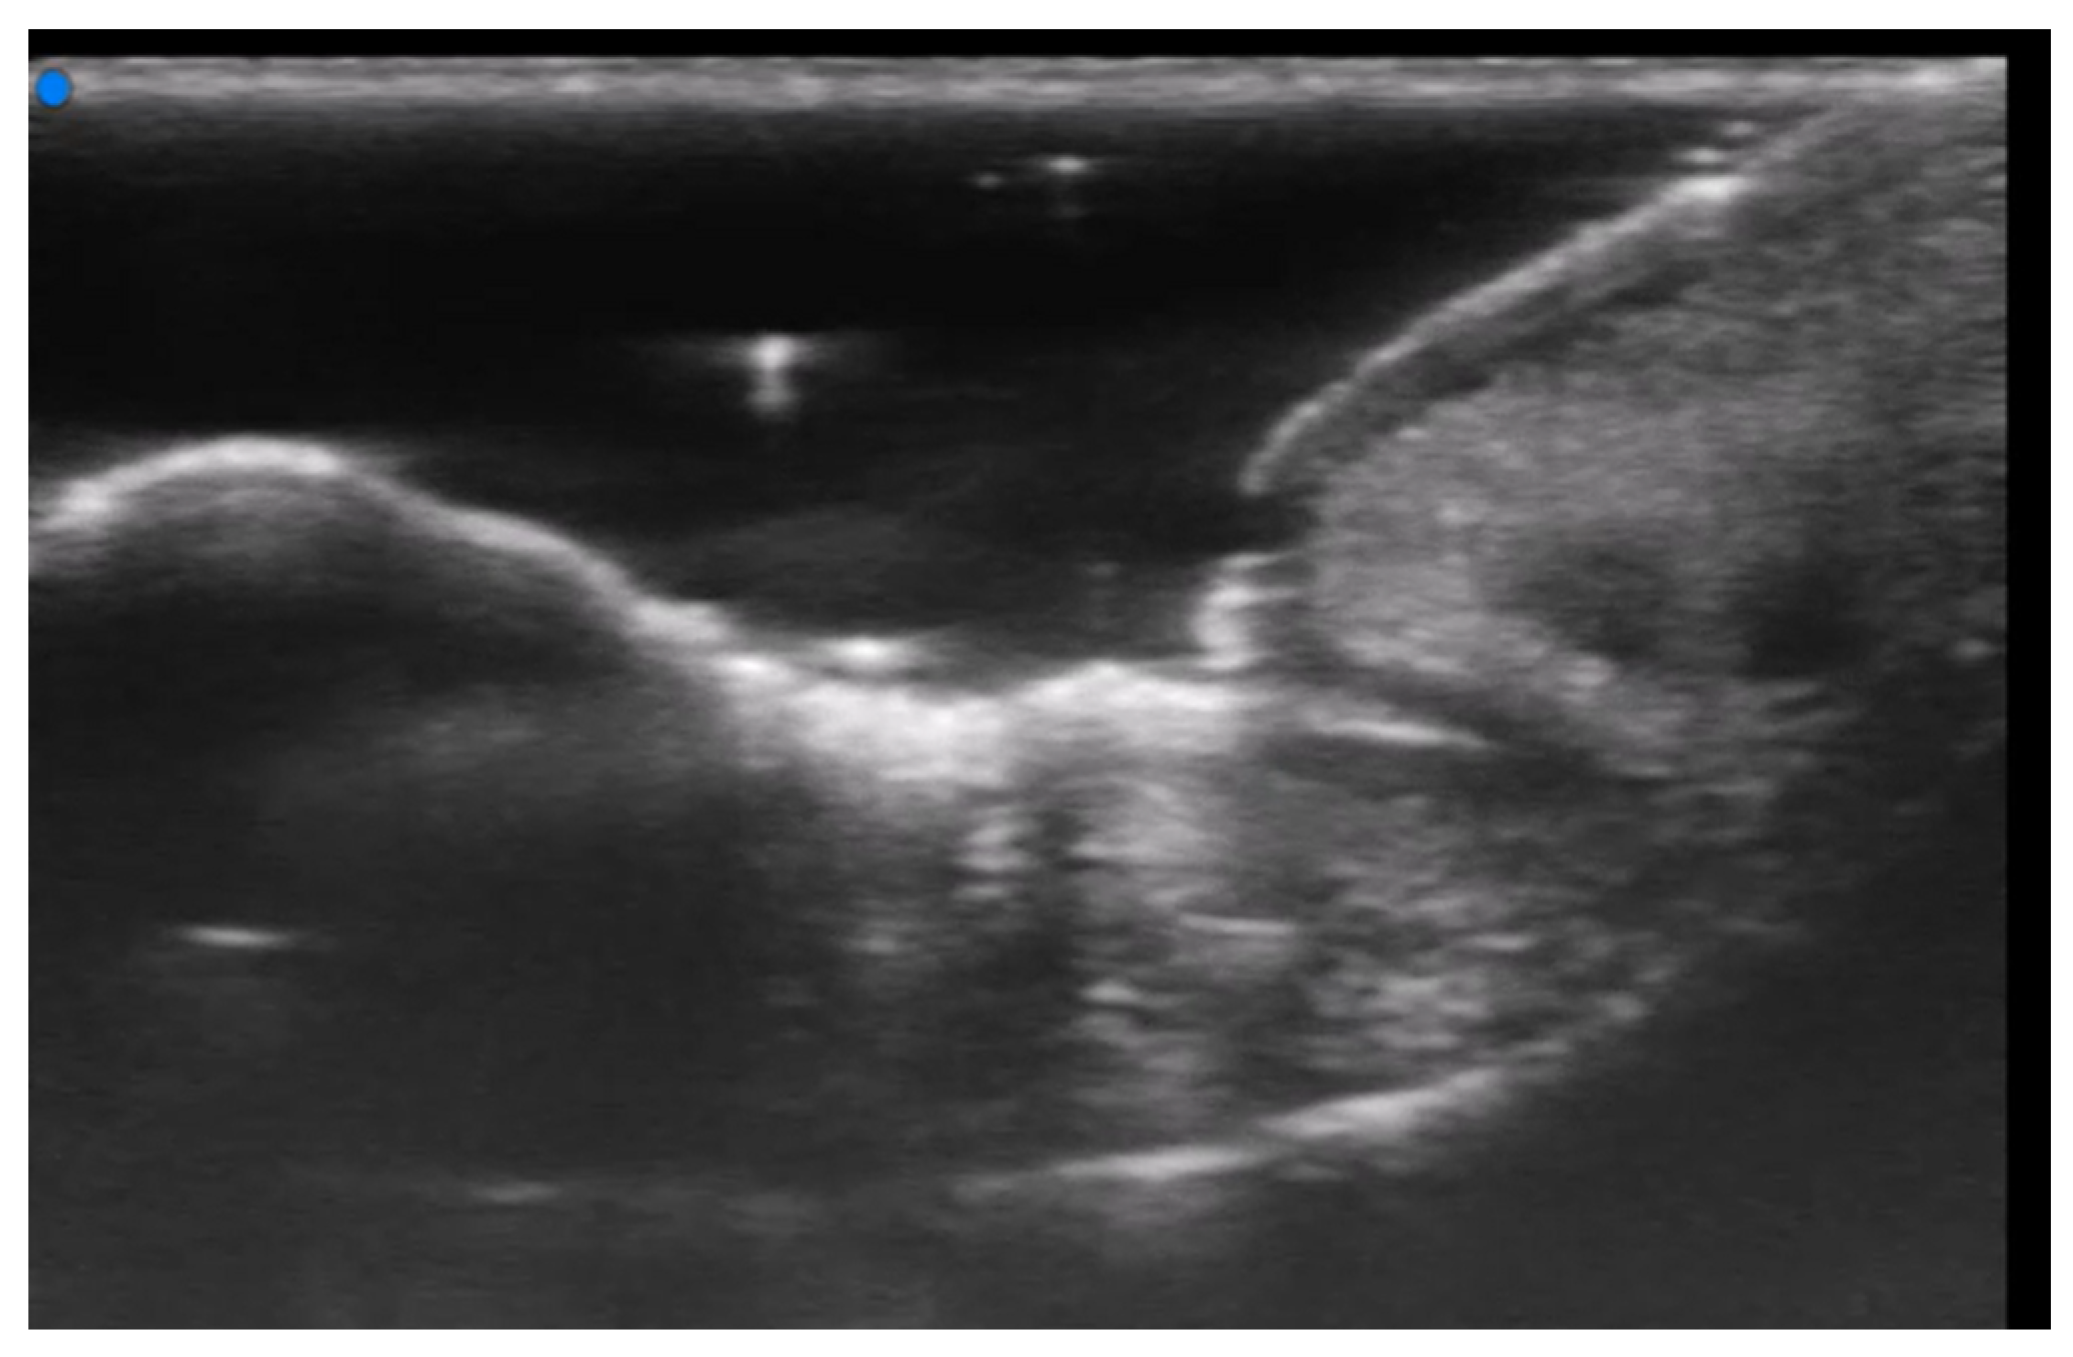

- Berritto, D.; Iacobellis, F.; Rossi, C.; Reginelli, A.; Cappabianca, S.; Grassi, R. Ultra high-frequency ultrasound: New capabilities for nail anatomy exploration. J. Dermatol. 2017, 44, 43–46. [Google Scholar] [CrossRef]

- Szymoniak-Lipska, M.; Polańska, A.; Jenerowicz, D.; Lipski, A.; Żaba, R.; Adamski, Z.; Dańczak-Pazdrowska, A. High-Frequency Ultrasonography and Evaporimetry in Non-invasive Evaluation of the Nail Unit. Front. Med. 2021, 8, 686470. [Google Scholar] [CrossRef]